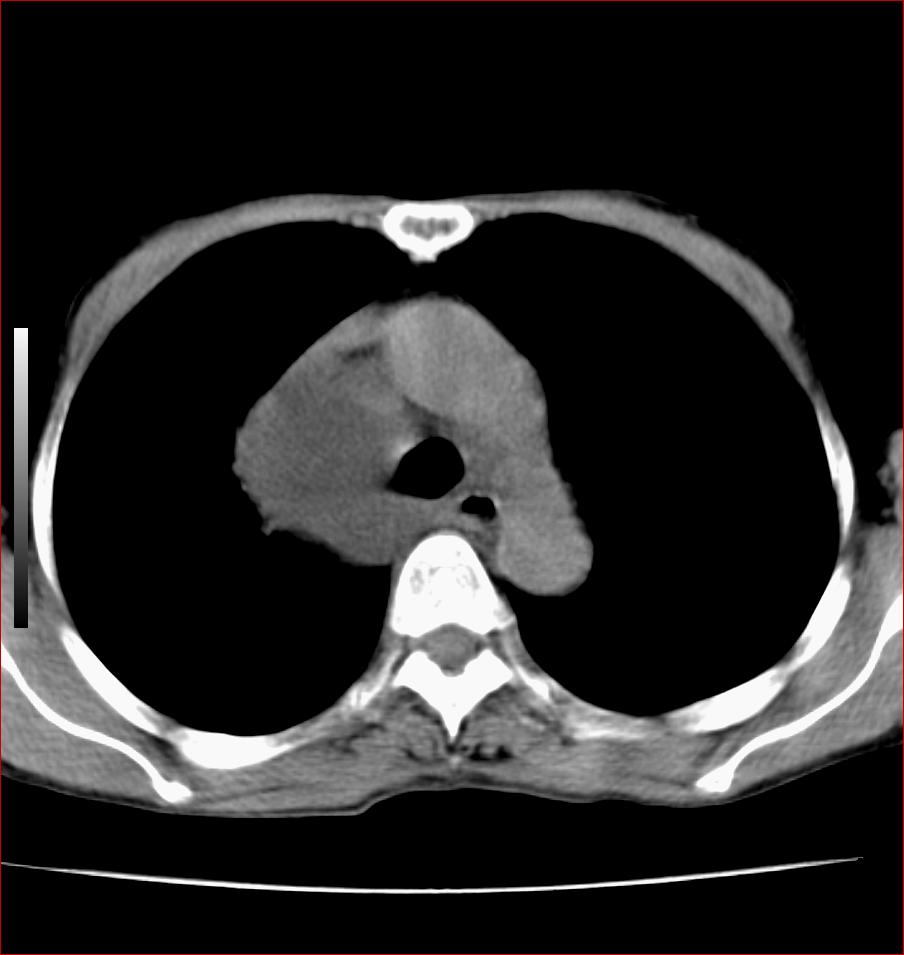

标题: CT17110:F56Y,纵隔囊肿;胸腺?淋巴?请各位老师看看 [打印本页]

标题: CT17110:F56Y,纵隔囊肿;胸腺?淋巴?请各位老师看看

女性患者 56 咽痛伴声嘶10+天入院。

右上纵隔囊性占位性病变;考虑支气管囊肿可能。

病变紧贴气管右壁,两者相互压迫,考虑支气管囊肿!

见相互挤压征,考虑气管囊肿,建议ct增强扫描